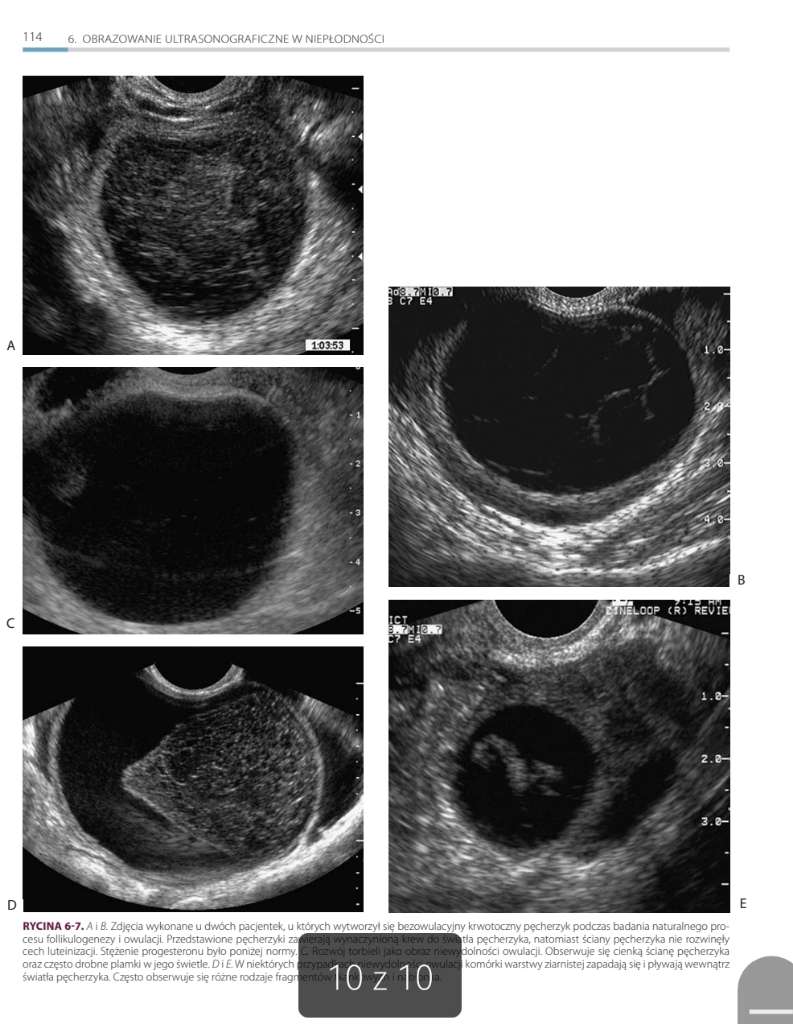

Dodaję zdj mojego USG z jednego z cykli kiedy miałam USG przed i po owulacji.

Jak dla mnie to te ciałko żółte wygląda jak jakiś zaburzony pęcherzyk bo ma jakieś kropki. 😅😂

Aktualna ginekolog stwierdziła, że nie do końca tak powinno wyglądać.

Wygląda jak nie ciałko żółte 😅 w sumie wygląda jak ten zluteinizowany pęcherzyk z artykułu, który czytałam...

Nie wiem czy będziecie widziały opisy pod zdjęciami a są dość istotne 🤔

I właśnie o tym mówię. Wg większości ginów to jest ciałko żółte i prog na to wskazuje- 6-7dni po "owulacji" był 19ng. A u mnie to zawsze- tzn jak mam monitoring po owu tak wygląda.

Dlatego mówię, że u mnie to podejrzewa gin ale nie może tego jednoznacznie stwierdzić. 😅

Tzn ta nowa dopiero zaczyna mnie leczyć i u niej już zostaję do końca mojej kariery staraczki więc dowiem się za kilka miesięcy czy to LUF czy taka moja natura.